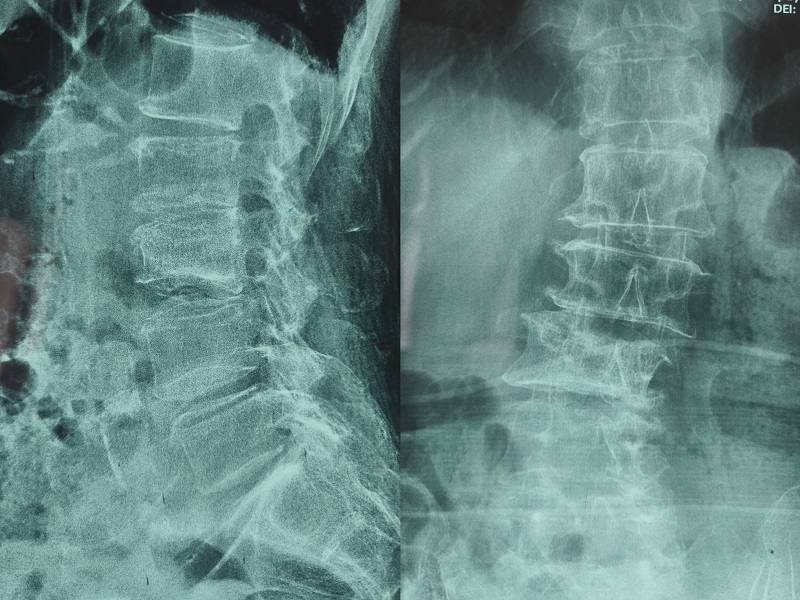

機(jī)器人輔助腰椎后路側(cè)彎矯形手術(shù)術(shù)后圖像

術(shù)后圖像